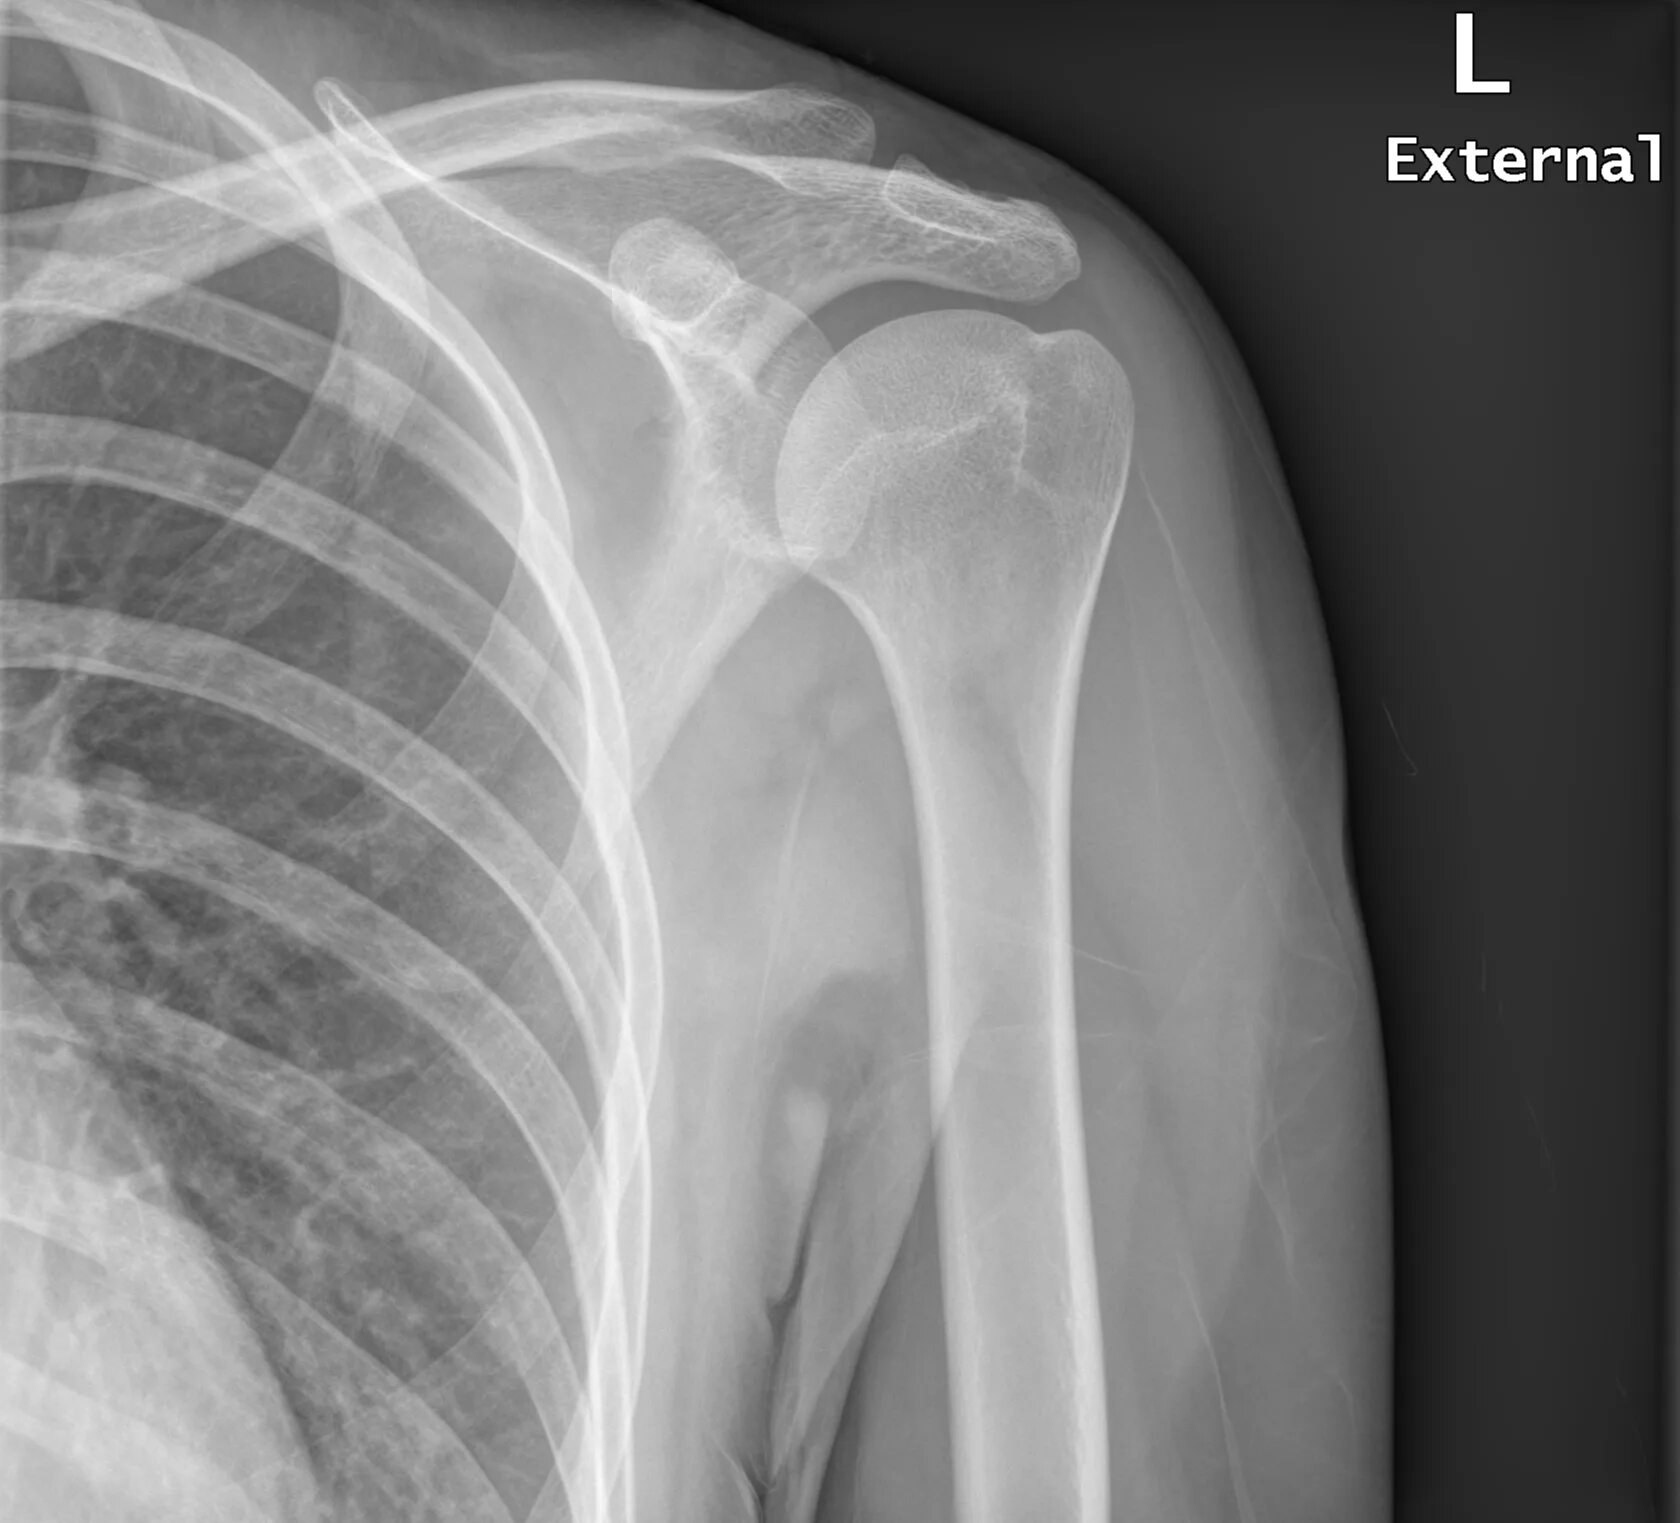

Source x rays